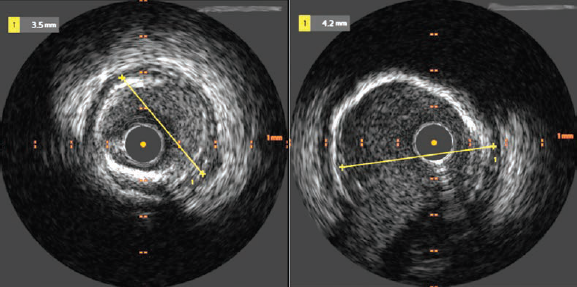

A 6 French right radial access was obtained and the left main coronary artery (LMCA) was cannulated. The first diagonal branch was wired and the LAD was wired with a second wire. Pre-dilation from the mid LAD back into the LMCA was performed with 2.0 x 20 mm semicompliant balloon. Intravascular ultrasound (IVUS) was then performed with the Refinity short-tip rotational IVUS catheter (Philips) in the mid LAD into the LMCA, and demonstrated fibrocalcific plaque with segments of circumferential calcium (Figure 2). The distal reference diameter was measured as 3.4 mm in the LAD and proximal reference diameter as 4.2 mm in the LMCA (Figure 3).